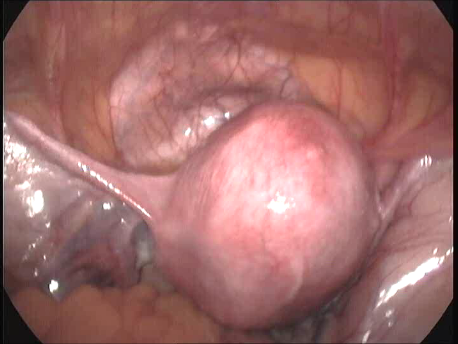

Endoscopy involves placing a small telescope into the human body through tiny incisions (3-5mm). The telescope can be placed into the abdomen via small tubes called ports (laparoscopy) or inside the uterus through the mouth of the uterus or cervix (hysteroscopy).

Various fine and delicate instruments are available through which complicated surgeries can be performed inside the abdomen or the uterus. In fact, endoscopic surgery has become the gold standard of surgery today. Since most of these instruments are being manufactured locally, the cost of endoscopy has also reduced significantly since its advent in the eighties.